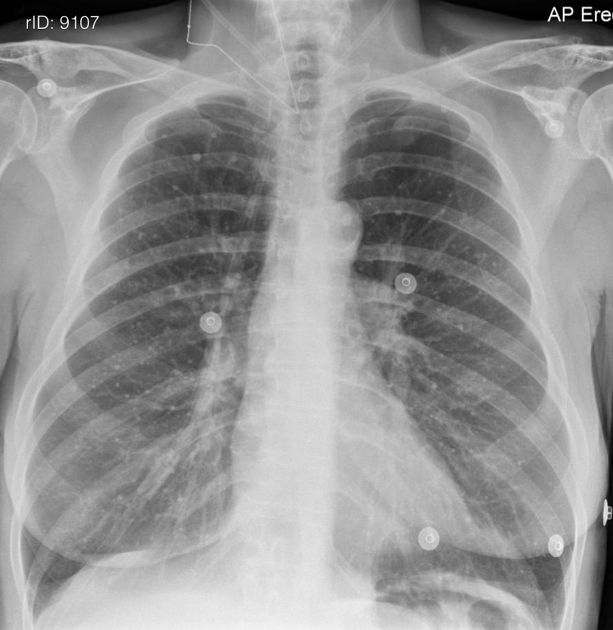

결핵(Tuberculosis, TB)은 Mycobacterium tuberculosis라는 박테리아에 의해 발생하는 전염병입니다. 결핵은 주로 폐에 영향을 주지만, 다른 부위에도 영향을 미칠 수 있습니다. 아래는 결핵의 주요 증상에 대한 설명입니다.

결핵(Tuberculosis, TB)은 Mycobacterium tuberculosis라는 세균에 의해 발생하는 전염병입니다. 이 박테리아는 공기를 통해 전파되며, 주로 감염된 사람이 기침이나 재채기를 통해 나오는 미세한 비말을 통해 다른 사람에게 전파됩니다. 다만, 모든 감염자가 환자가 되지는 않습니다. 일부 사람들은 박테리아에 노출되어도 결핵에 걸리지 않을 수 있습니다.

이러한 세균 감염은 대개 폐에서 발생하지만, 다른 부위에도 영향을 줄 수 있습니다. 결핵은 대개 폐에 집중되어 "폐결핵"이라고도 불리며, 폐 이외의 부위에 생기는 경우도 있습니다. 박테리아가 폐 이외의 장기에 감염되는 경우는 "부속기관 결핵"이라고도 불립니다.